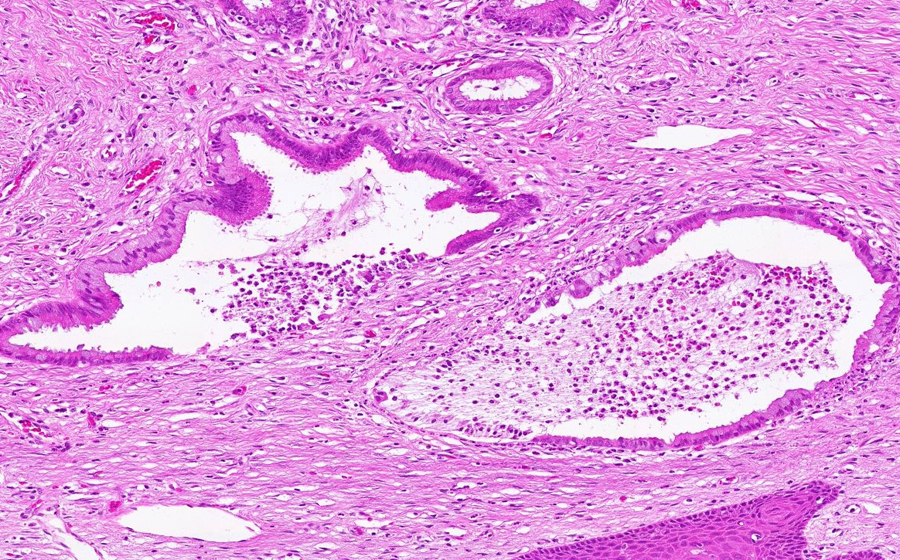

Slide 3: Chronic cervicitis and metaplasia

Histologic section of cervix from a patient with chronic cervicitis (click here to review normal tissue)

Image 11 - 50X

Slide 3 - Image 11